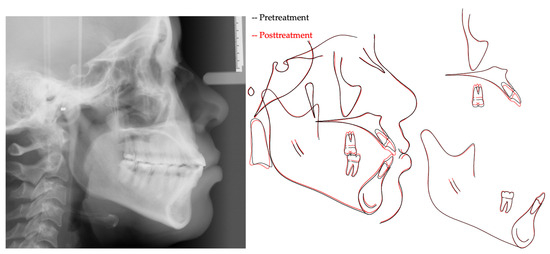

| Measurement | A (Initial) | B (Final) | Difference (A-B) |

|---|---|---|---|

| SNA° | 89.6 | 89.3 | 0.3 |

| SNB° | 84.7 | 84.6 | 0.1 |

| ANB° | 4.9 | 4.7 | 0.2 |

| SN-MP° | 38.7 | 37.5 | 1.2 |

| FMA° | 26.3 | 25.3 | 1.0 |

| UI TO NA mm | 6.8 | 5.7 | 1.1 |

| UI TO SN° | 119.6 | 115.1 | 4.5 |

| LI TO NB mm | 11.0 | 10.5 | 0.5 |

| LI TO MP° | 97.8 | 96.0 | 1.8 |

| U Lip to E-Line | −1.3 | −1.3 | 0.0 |

| L Lip to E-Line | 2.7 | 2.5 | 0.2 |